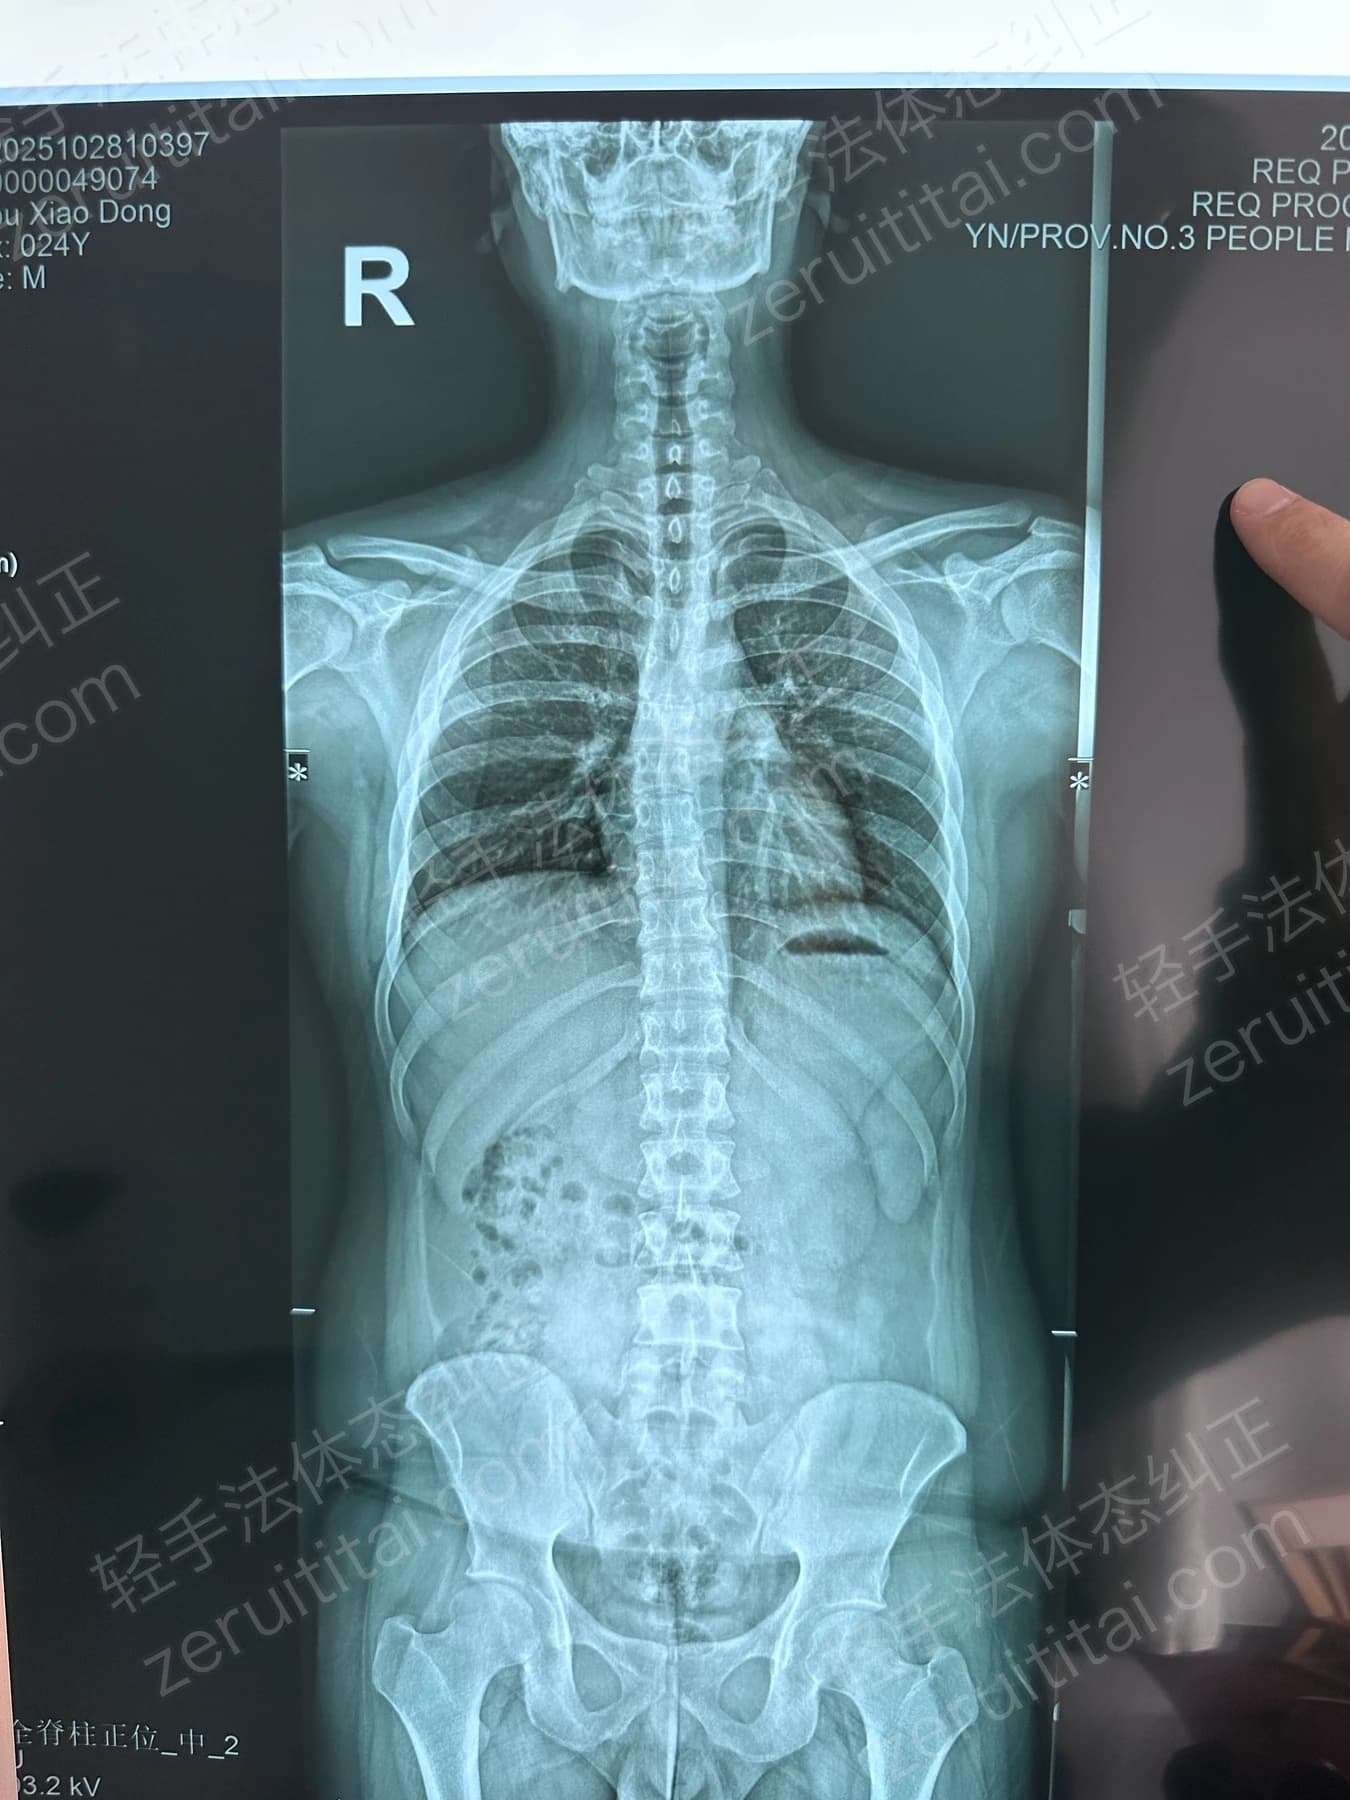

2024.12.18

第 6 次记录

右侧对比

第 6 次记录2024.12.18

正面 X 光